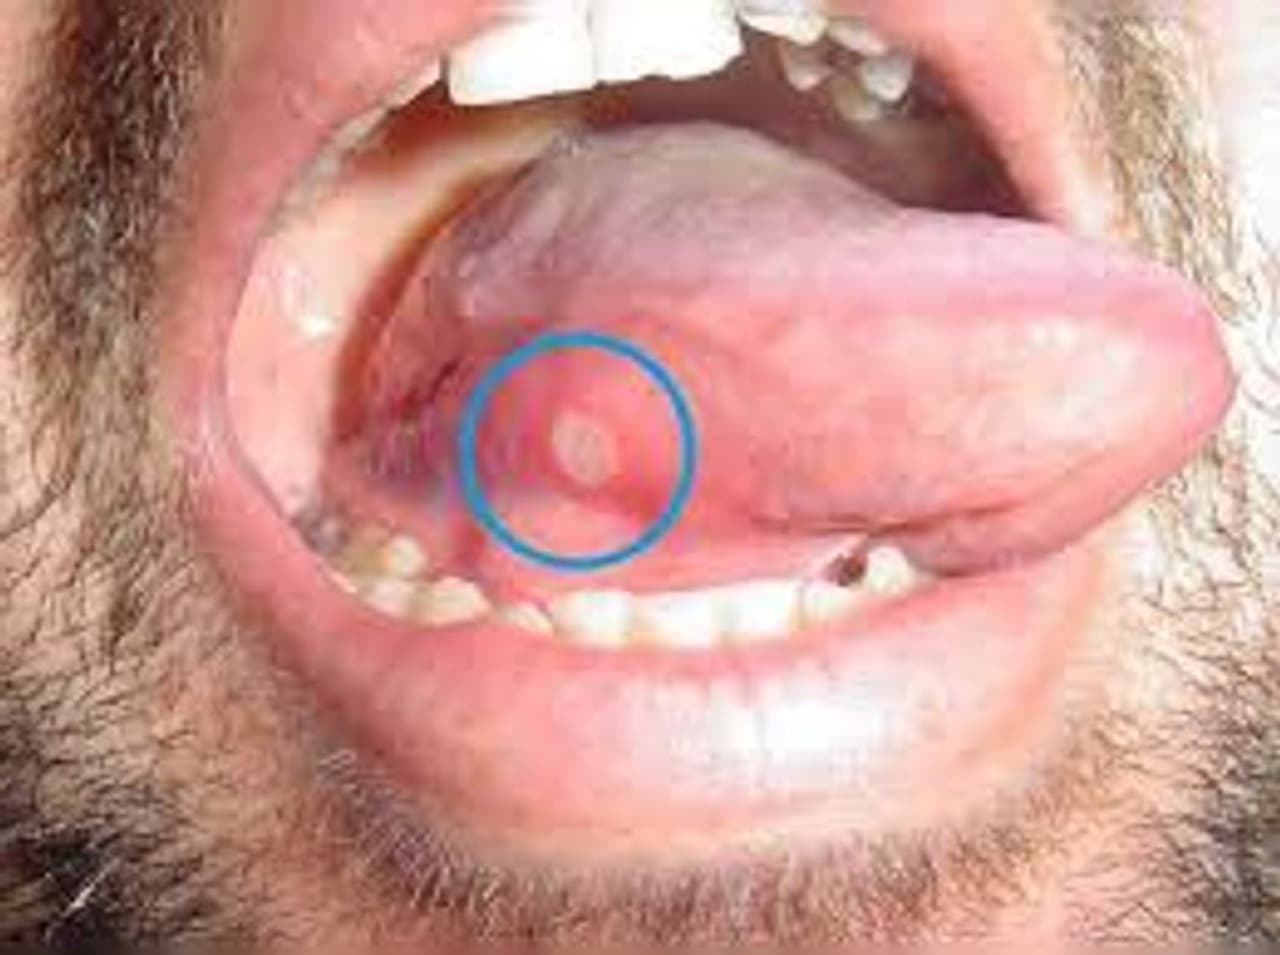

Mouth Ulcers: வாய்புண் தொல்லையால் அவதியா..? உடனடி தீர்வுக்கு இந்த 5 வீட்டு மருந்துகள் கை கொடுக்கும்..!

How to get rid of mouth ulcers fast at home: பசித்தால் சாப்பிடக்கூட முடியாமல், வாய்புண் தொல்லை உங்களை பாடாய் படுத்துகிறதா..? வீட்டில் இருக்கும் இந்த மருந்துகள் மூலம் நீங்கள் சுலபமான முறையில் தீர்வு காணலாம்.

சிறு குழந்தை முதல் வயதானவர்கள் வரை நம்மில் பலர் எதிர்கொள்ளும் மிக முக்கிய பிரச்சனைகளில் ஒன்று வாய்ப்புண். சில நேரம் பசித்தால் சாப்பிடக்கூட முடியாமல் வாய்ப்புண் வந்து தொல்லை கொடுக்கும். வாய் பகுதியின் ஓரத்தில் புண்கள் வருவது, கீழ் மற்றும் மேல உதடுகளின் மேல் மற்றும் உள்புறத்தில் புண் வருவது என வாய்ப்புண் பல விதங்கள் உண்டு.